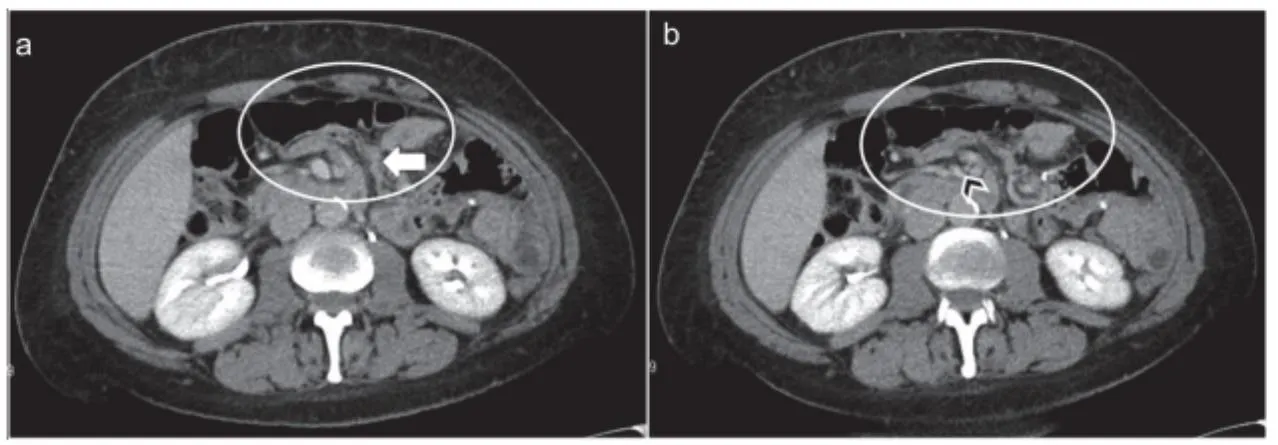

Swirled mesentery

•

Hurricane eye

: distal tubular mesentery with surrounding small loops

SMV beaking / Criss cross appearance

: Mesenteric swirl, small bowel obstruction 이 internal hernia진단에 있어 가장 정확도가 높다고

알려져 있으나, SMV의 직경이 새부리 모양처럼 줄어드는 SMV beaking sign 역시 흔하게 나타나는 sign이다.

a,b : 소장 loop가 복부 전벽에 인접하여 있다. SMV의 직경이 좁아져 beaked 모양으로 보인다 (화살촉)

herniated mesenteric loop 가 버섯 모양처럼 보인다.